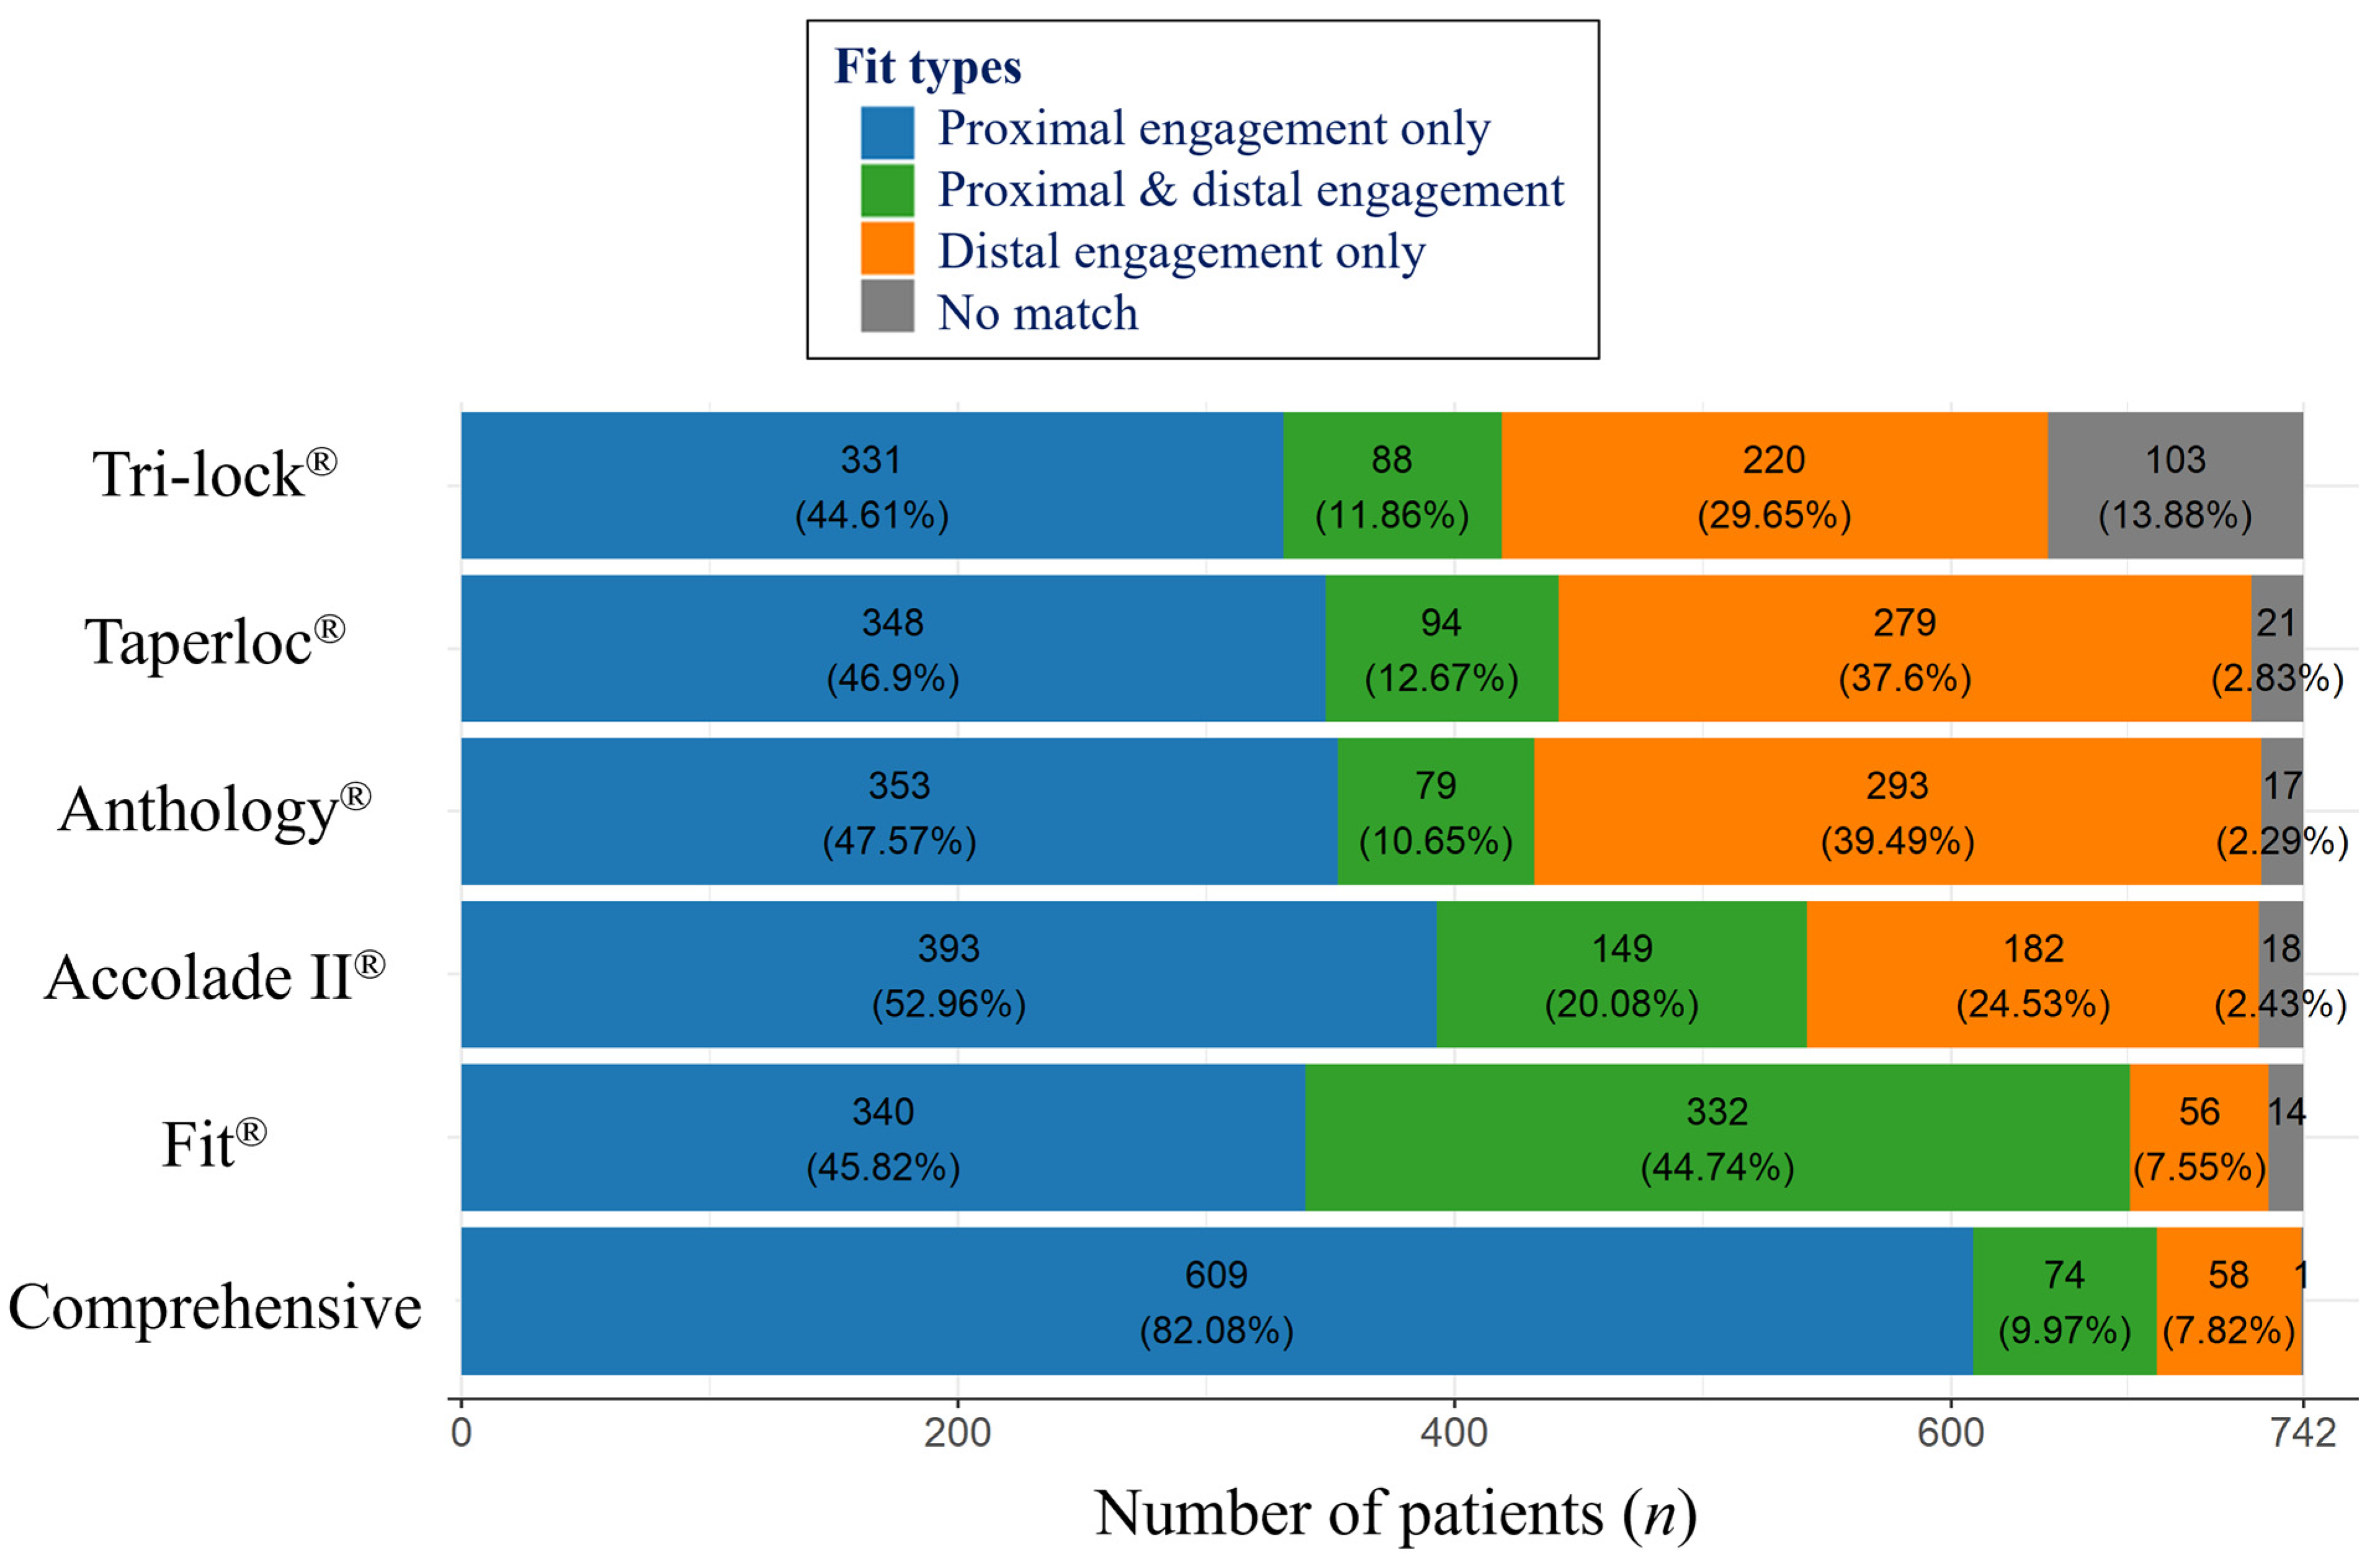

3.3. Fit Analysis